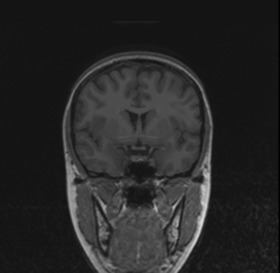

BRAINSMush uses the Maximize Uniformity Summation Heuristic(MUSH) optimizer, as developed at the University of Iowa, to extract the brain and surface CSF from a multi-modal imaging study. It forms a linear combination of multi-modal MR imaging data to make the signal intensity within the brain as uniform as possible. This resulting image is then thresholded to obtain the brain and surface CSF region.

This method was applied to a sample of 20 MR brain scans and its results were compared to those obtained by 3dSkullStrip, 3dIntracranial, BET and BET2. The average Jaccard metrics for the twenty subjects was 0.66(BET), 0.61(BET2), 0.88(3dIntracranial), 0.91(3dSkullStrip) and 0.94(MUSH).